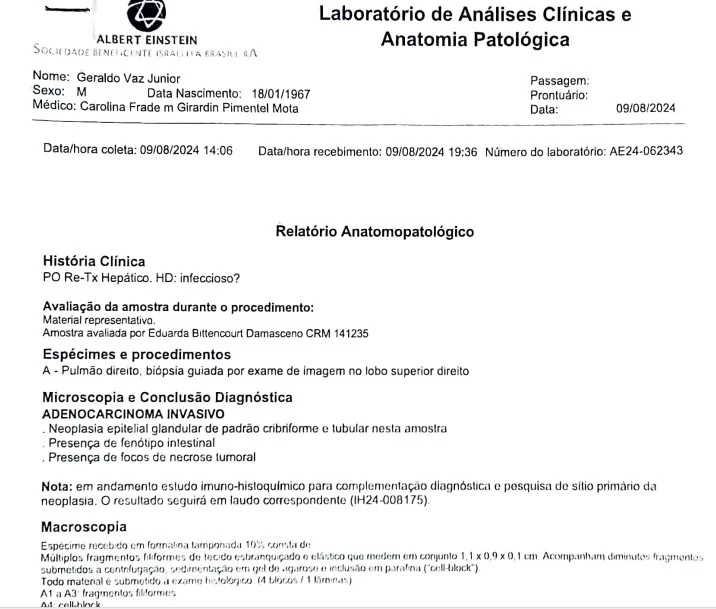

relatório anatomopatológico diagnostica o tipo e o grau do tumor

7 de 7

No início de agosto de 2024, veio mais um susto: foi detectada metástase no pulmão do paciente. A conclusão diagnóstica indicou um adenocarcinoma invasivo com as mesmas características das células cancerígenas do fígado transplantado.

“Isso sugere que a doadora já tinha um câncer que não foi detectado antes da doação, e pequenas células desse tumor estavam presentes no fígado transplantado”, explicou Caroline.